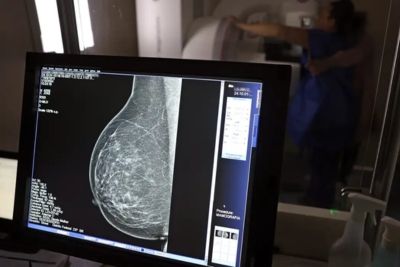

Outubro é mundialmente conhecido pela cor rosa, que simboliza a luta contra o câncer de mama. No Brasil, os números são preocupantes: segundo o Instituto Nacional de Câncer (INCA), em 2025, cerca de 74 mil novos casos devem ser diagnosticados, o que faz desse o tipo mais comum entre as mulheres — responsável por aproximadamente 1 em cada 3 casos de câncer registrados no país.

Os avanços no tratamento são importantes, mas a chave está na prevenção e no diagnóstico precoce. “Quando o câncer é descoberto nos seus estágios iniciais, a cura em alguns deles pode chegar a 100%”, explica Maria Celestina Bonzanini Graziotin, enfermeira entrevistada pelo Programa Viva a Vida da Pastoral da Criança. Ela reforça que procurar o médico regularmente e realizar os exames de rastreamento são atitudes que podem salvar vidas.